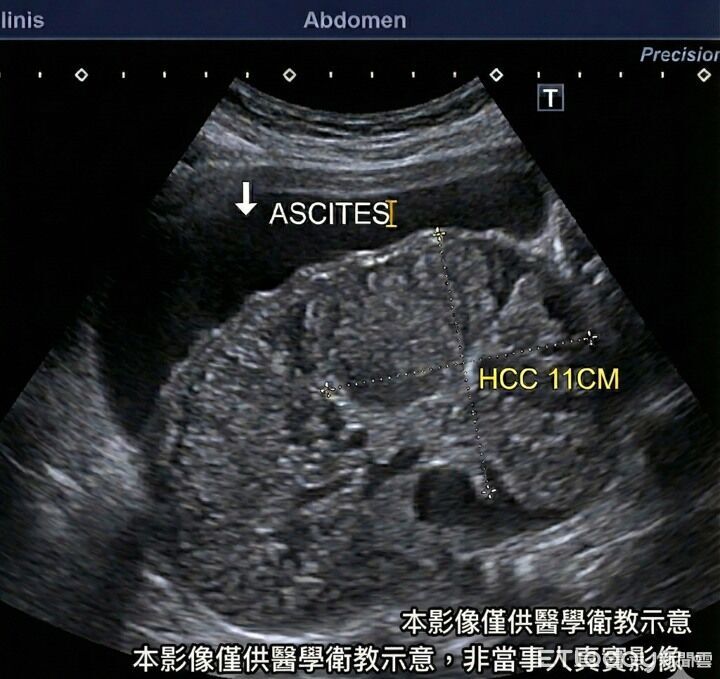

▲男子不只被檢查出患有肝硬化,還有顆11公分的巨大肝腫瘤。(示意圖/非當事人影像/卓韋儒醫師提供)

腸胃不適別輕忽!一名40歲男子因腹脹求診,原以為只是脹氣、拿點藥就好,但醫師卓韋儒一見到他「臉色不對、肚子大得不自然」,心中警鈴瞬間大響。緊急掃超音波後,竟驚見滿肚子腹水,影像顯示為嚴重肝硬化,還有一顆11公分的巨大肝腫瘤,確診罹患肝癌。病情遠超預期,讓診間氣氛瞬間凝重。